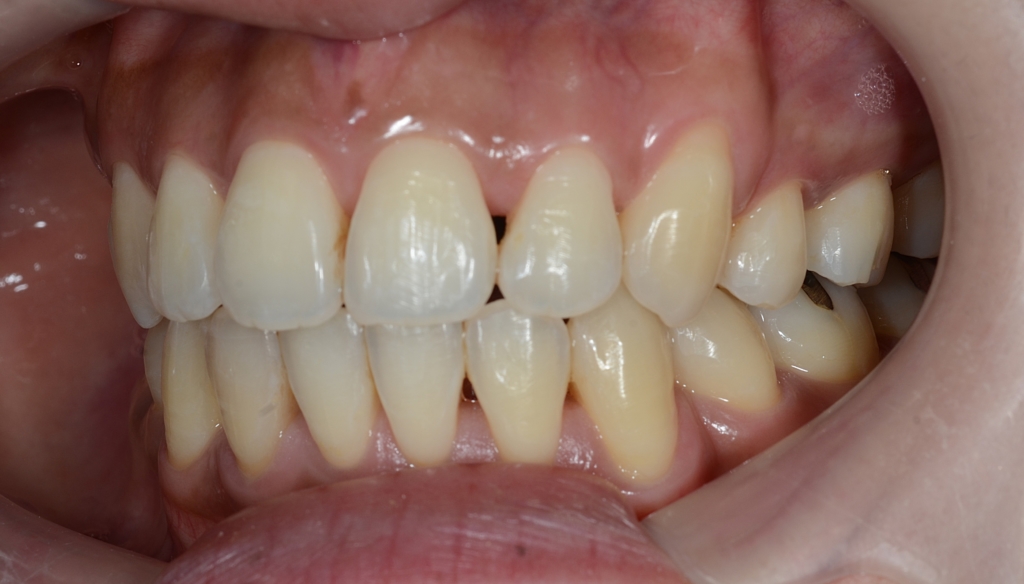

【After】

あらためて、矯正治療前後の歯並びと口元の変化を比べてみましょう。

まずは、歯並びの変化です。

今回は、歯並びをきれいにすることが一番! 口元の変化はあわよくばを狙った二番!でしたが、

歯並びはもちろん、口元を多少なりともスッキリさせることが出来、患者さんにも喜んでもらえました。

(お口を閉じるのが楽になったそうです)